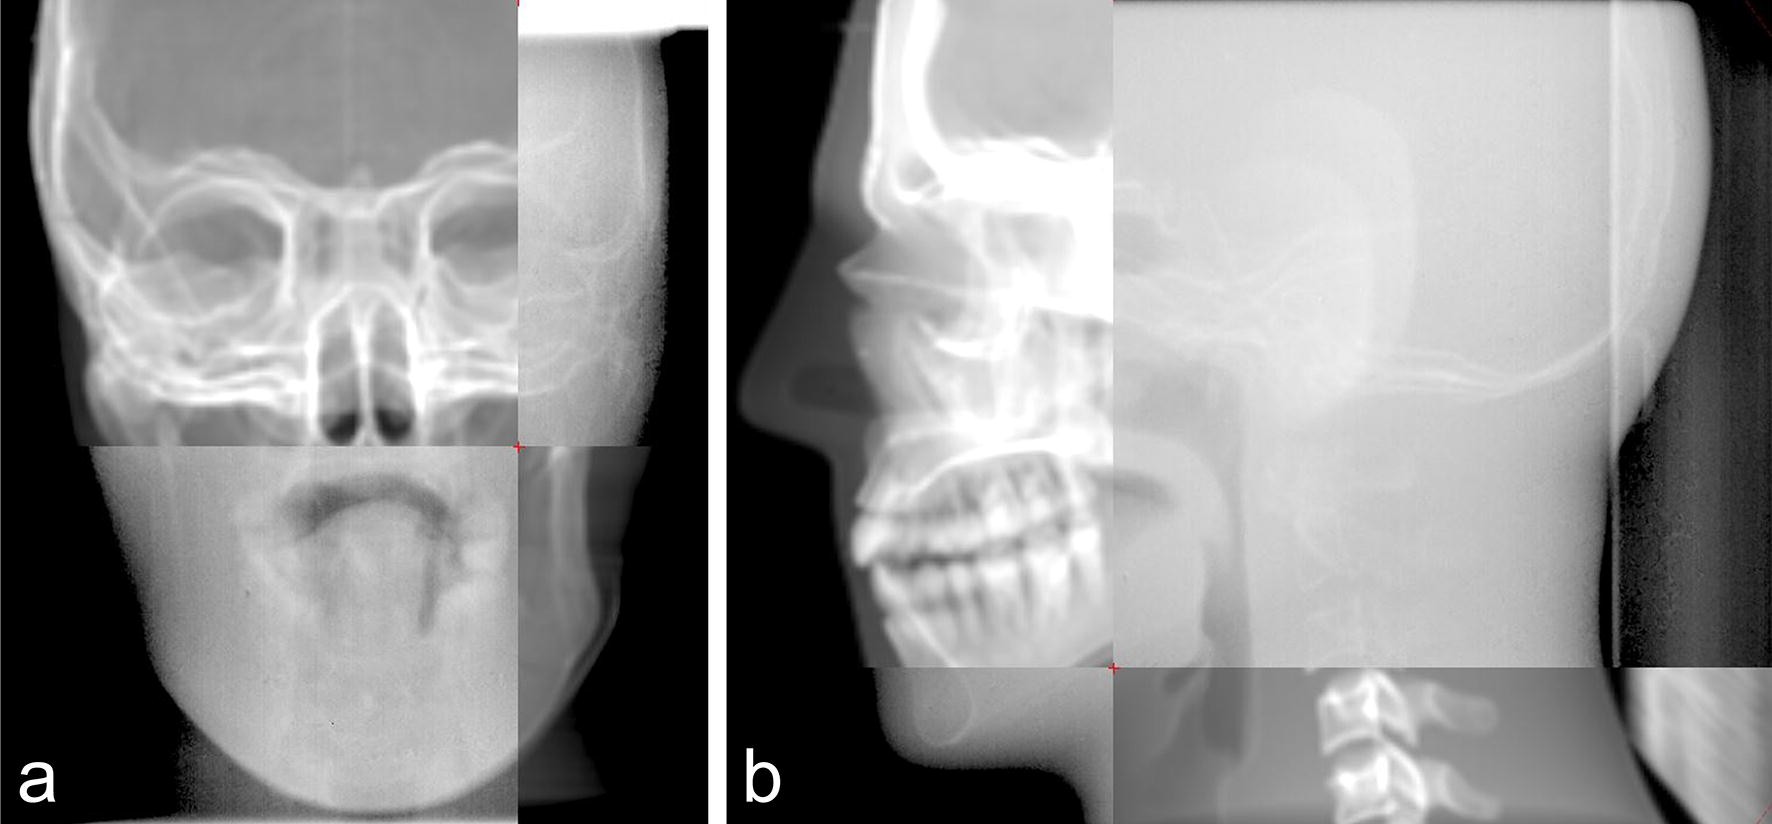

Figure 5

The traditional registration method of EPID and DRR images through the split window: (a) fusion images of anteroposterior view, (b) fusion images of lateral view.